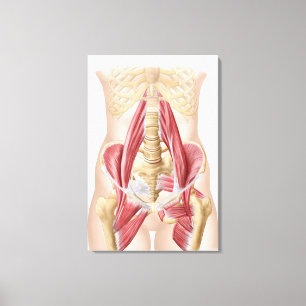

Poster Músculo-esqueleto da anca 3

Preço32,20 €